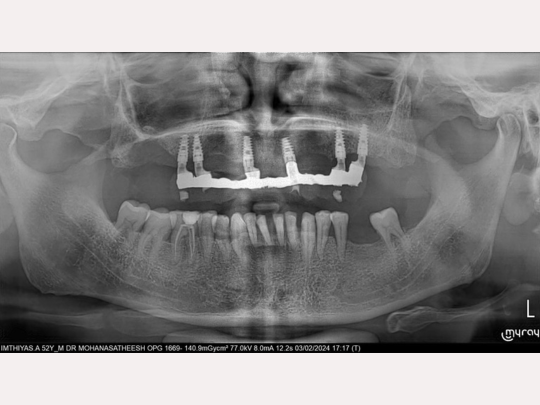

Implant

Before and After